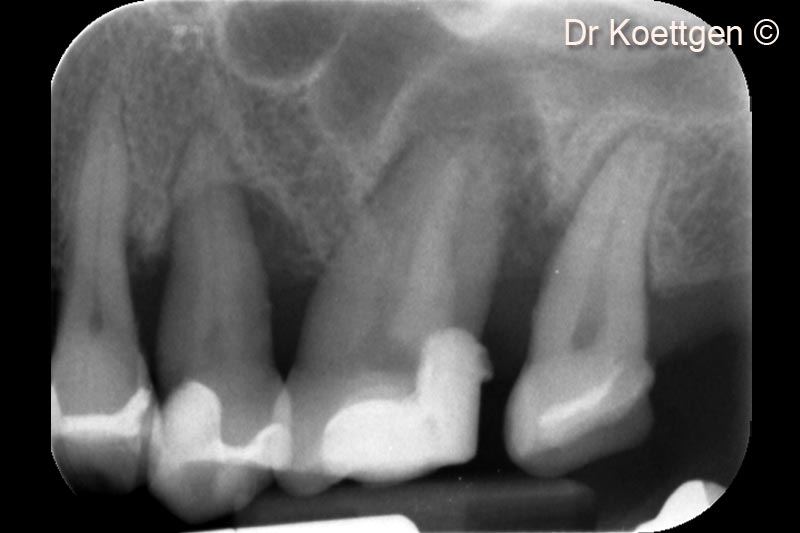

2. Initial x-ray